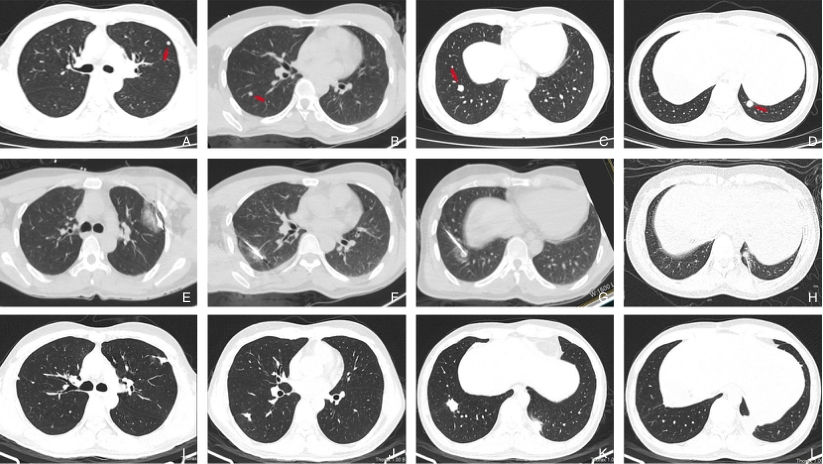

图4 33岁男性HCC患者在手术11个月后出现双肺转移,共接受了3次消融治疗,处于NED状态 A-C:手术后11个月,左肺及右肺出现转移灶;D:第2次消融术后4个月新出现的左下肺转移结节;E:CT引导下的左肺结节微波消融术(第1次);F-G:CT引导下的右肺结节微波消融术(第2次);H:CT引导下的左下肺结节微波消融术(第3次);I-L:第3次消融术后9个月复查,病灶缩小为纤维条索状Fig.4 A 33-year-old male HCC patient developed bilateral pulmonary metastases 11 months after surgery and underwent three ablation procedures, remaining in an NED state A-C: Metastatic lesions in the left and right lungs detected 11 months after surgery; D: A new metastatic nodule in the left lower lung detected 4 months after the second ablation; E: CT-guided microwave ablation of the left lung nodule (first ablation); F-G: CT-guided microwave ablation of the right lung nodule (second ablation); H: CT-guided microwave ablation of the left lower lung nodule (third ablation); I-L: Follow-up 9 months after the third ablation showing the lesions reduced to fibrous cord-like changes